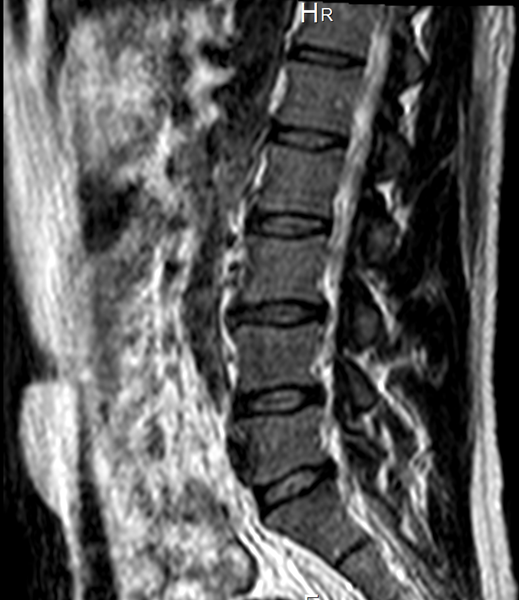

RM - ¿Alguien sabría decir si existe alguna protrusión discal?

La mutua mandó hacerme una Resonancia Magnética y el informe en resumen dice: Sin hallagos patológicos.

¿Alguien podría decir si existe alguna protrusión discal que esté causando el dolor lumbar, glúteo, muslo izq... Que padezco?